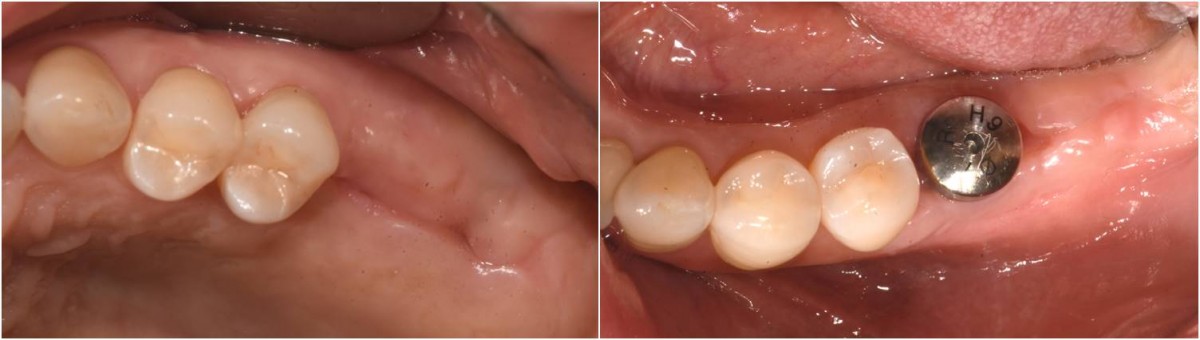

A 55-year-old female patient had

bilateral problems in both jaws.

It was decided to proceed with implant-supported restoration in the left molar part first.

She had been taking hypertension medication for a long time.